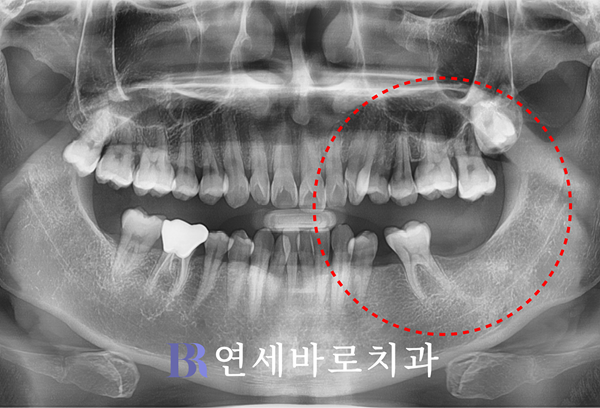

오늘 소개할 환자분께서는

하악 왼쪽의 어금니 두 곳이

탈락한 상태로 오셨습니다.

해당 부위 치조골이 다소

밑으로 내려간 모습이었으며,

이외에 여러 가지 문제가

다소 복잡하게 얽혀 있었습니다.

우선 제1대구치가 한쪽으로

기울어진 상태였는데요.

그러면서 제2소구치 부분에

매식체가 들어갈 공간이

상당 부분 소실되었습니다.

그래서 임플란트를 심으려면

그만큼 다른 자연치아를

삭제할 수 밖에 없었습니다.

게다가 사랑니 때문에 밀려

윗니 1개가 내려왔는데,

정상적인 교합을 완성하려면

영구치를 희생시키면서

높이를 맞춰주어야 했습니다.